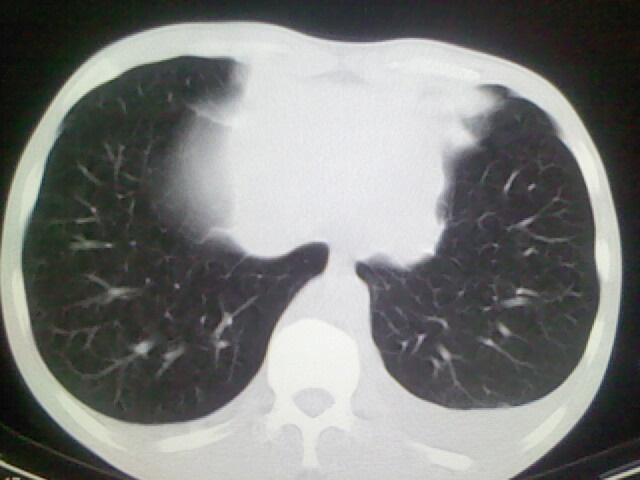

以下是引用杀毒软件在2008-9-3 6:11:00的发言:[br]侵袭性胸腺瘤------一般不侵到气管旁[br][br]考虑----纵隔淋巴瘤,心包及胸膜受累

以下是引用随光逐影在2008-9-3 7:07:00的发言:[br]1)考虑淋巴瘤可能。2)双侧胸腔积液(以左侧为甚)。3)心包积液。